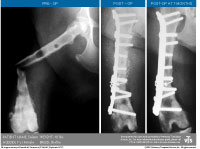

Osteoallograft Orthomix Case Study with Shaft Section (PDF: 424 KB)

Hoffer M, Griffon D, Schaeffer D, Johnson A, Thomas M. Clinical applications of demineralized bone matrix: A retrospective and case-matched study of 75 dogs. Vet Surg. 37:639-647, 2008 |

Lafaver S, et al

Tibial tuberosity advancement for stabilization of the canine cranial cruciate ligament-deficient stifle joint: […].

Veterinary Surgery. 36:573-586, 2007. |